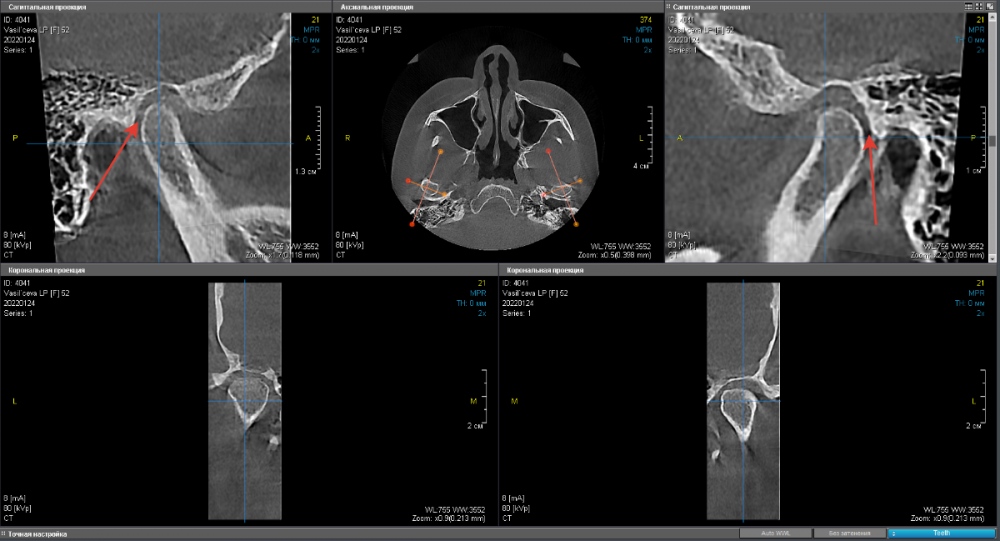

Произведено: функциональная диагностика.  Выставлено новое терапевтическое положение нижней челюсти. Изготовлен байт(силиконовая накуска) и пациент отправлен на КТ

КТ ДО(до диагностики):

336494961_.thumb.png.684f55cf9298867e9822af0a23afacd8.png

КТ ПОСЛЕ(с байтом в полости рта):

1179766551_.thumb.png.b843c7b5a257dab69d353cd58d83e3fe.png

В целом хорошо. Пальпация стала безболезненной, из биламинарной зоны мыщелок убрали - одни плюсы. Изготовили капу, составили план лечения и погнали..